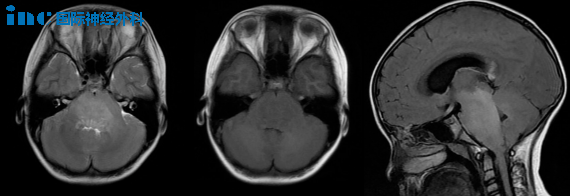

3. 肿瘤恶化快,要先手术吗?

9岁女孩被诊断为脑干病变和梗阻性脑积水。弥漫性脑干病变累及延髓、脑桥和中脑下部,第四脑室受到压迫,导致幕上脑积水。立体定向活检结果显示为儿童弥漫性中线胶质瘤,H3K27改变,WHO4 级。鉴于其30%的高Ki67指数,肿瘤生长速度相当快。

Rutka教授:根据所提供的信息,患儿的肿瘤属于弥漫性内生型脑桥胶质瘤(DIPG),不建议进一步手术切除肿瘤,这也是无法做到的。这个阶段需要进行放射治疗。两种较好选择是传统的三维适形体外放射治疗和质子束治疗。